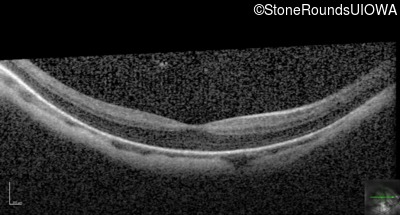

Optical Coherence Tomography - Right - 20/32 -1

Exemplar / OCT Stack

OCT Stack